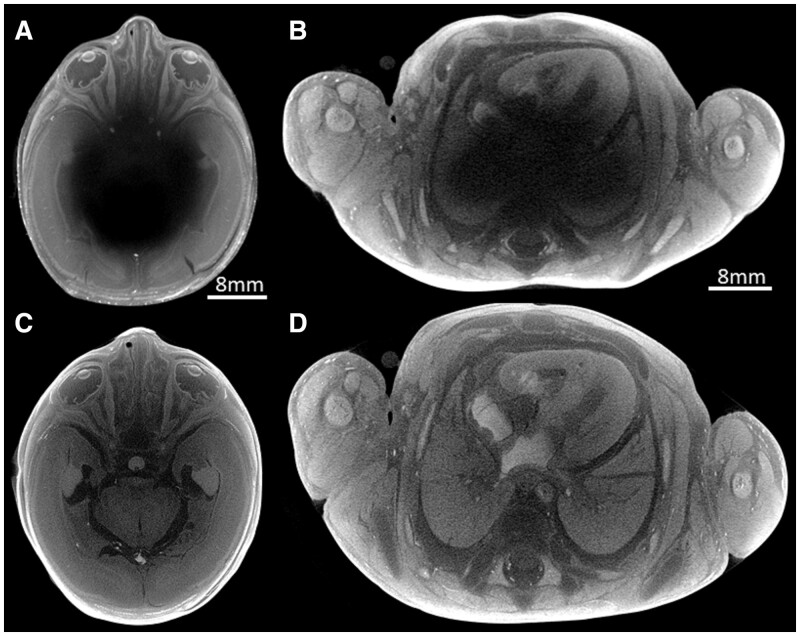

Abstract Image